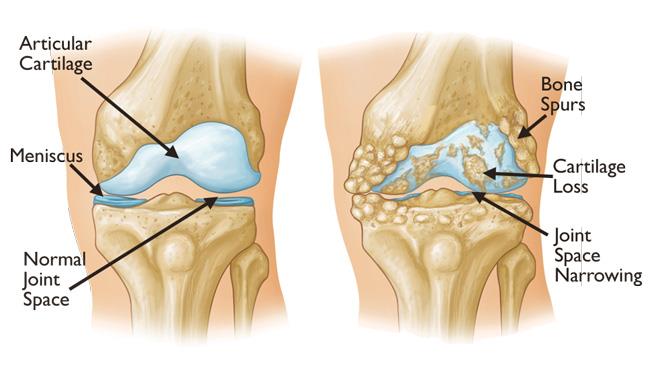

Sendi merupakan penghubung antar tulang yang berperan penting dalam menggerakkan tulang dengan mudah. Namun, karena faktor usia dan aktivitas sehari-hari, maka pelumas yang melindungi sendi semakin menurun intensitasnya, sehingga tulang rawan menjadi rusak dan mengalami keausan.

Pada OA lutut, gejala yang paling sering dirasakan yakni rasa nyeri sehingga lutut terasa sakit saat berdiri maupun berjalan. Berikut ini adalah gejala OA yang paling umum, antara lain:

- Kekakuan dan bengkak pada sendi

- Sendi terasa sakit ketika menggerakkannya

- Muncul benjolan di area sendi yang terdampaK

- Terdengar bunyi gemeretak (krepitasi) saat menggerakkan sendi

- Melemahnya otot di sekitar persendian yang sakit

- Menurunnya fungsi dan kemampuan menggerakkan sendi

- Terbentuknya taji tulang saat tulang bergesekan

Ketika mengalami OA lutut, Anda mungkin akan kesulitan dalam melakukan rutinitas harian. Bahkan, jika ingin menekuk atau meluruskan kaki itupun akan terasa sangat menyakitkan. Untuk itu, penting untuk mewaspadai gejalanya dan segera lakukan pengobatan.